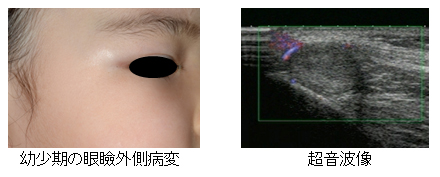

腫瘍切除後の再建外科:最近の進歩 (形成外科advanceシリ-ズ)